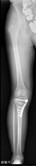

人工膝関節置換術、高位脛骨骨切り術

高位脛骨骨切り術後